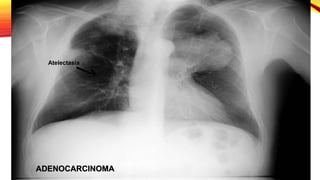

EXPLORACIONES COMPLEMENTARIAS

Radiografia de tórax

Ensanchamiento

hiliar

Atelectasia

Condensación

distal

Neumonitis

infecciosa

secundaria

Adenocarcinoma

• Se presenta como nódulo o masa de distribución

periférica y ocasional presencia de broncrograma aéreo.

• Carcinoma bronquioalveolar presenta broncograma

aéreo y puede presentar cavitación

EXPLORACIONES COMPLEMENTARIAS Radiografia detórax Ensanchamiento hiliar Atelectasia Condensación distal Neumonitis infecciosa secundaria Farreras & Rozman Medicina Interna 17 edicion, capitulo 81, Pag 726.

Carcinoma de célulaspequeñas • Localización prehiliar en el 80% y se asocia a adenopatías mediastinicas. Carcinoma escamoso • Masa central de gran tamaño que a menudo se cavita. Adenocarcinoma • Se presenta como nódulo o masa de distribución periférica y ocasional presencia de broncrograma aéreo. • Carcinoma bronquioalveolar presenta broncograma aéreo y puede presentar cavitación Farreras & Rozman Medicina Interna 17 edicion, capitulo 81, Pag 726.